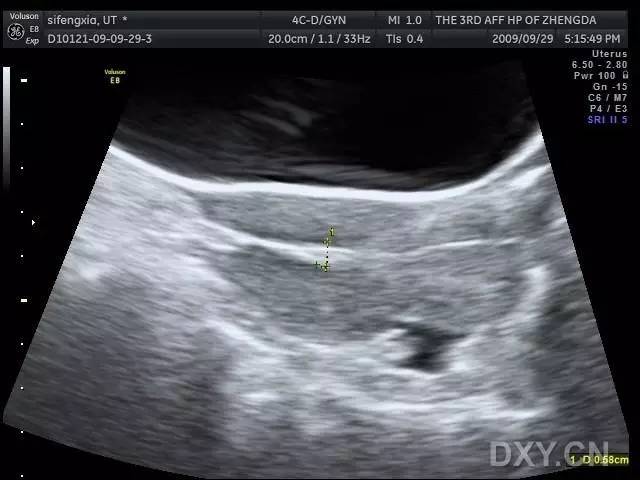

子宫穿孔的彩超图片

子宫穿孔的彩超图片,子宫穿孔诊断书图片

子宫穿孔

子宫穿孔的超声诊断

子宫穿孔超声表现图

子宫穿孔超声图片

子宫穿孔彩超下表现